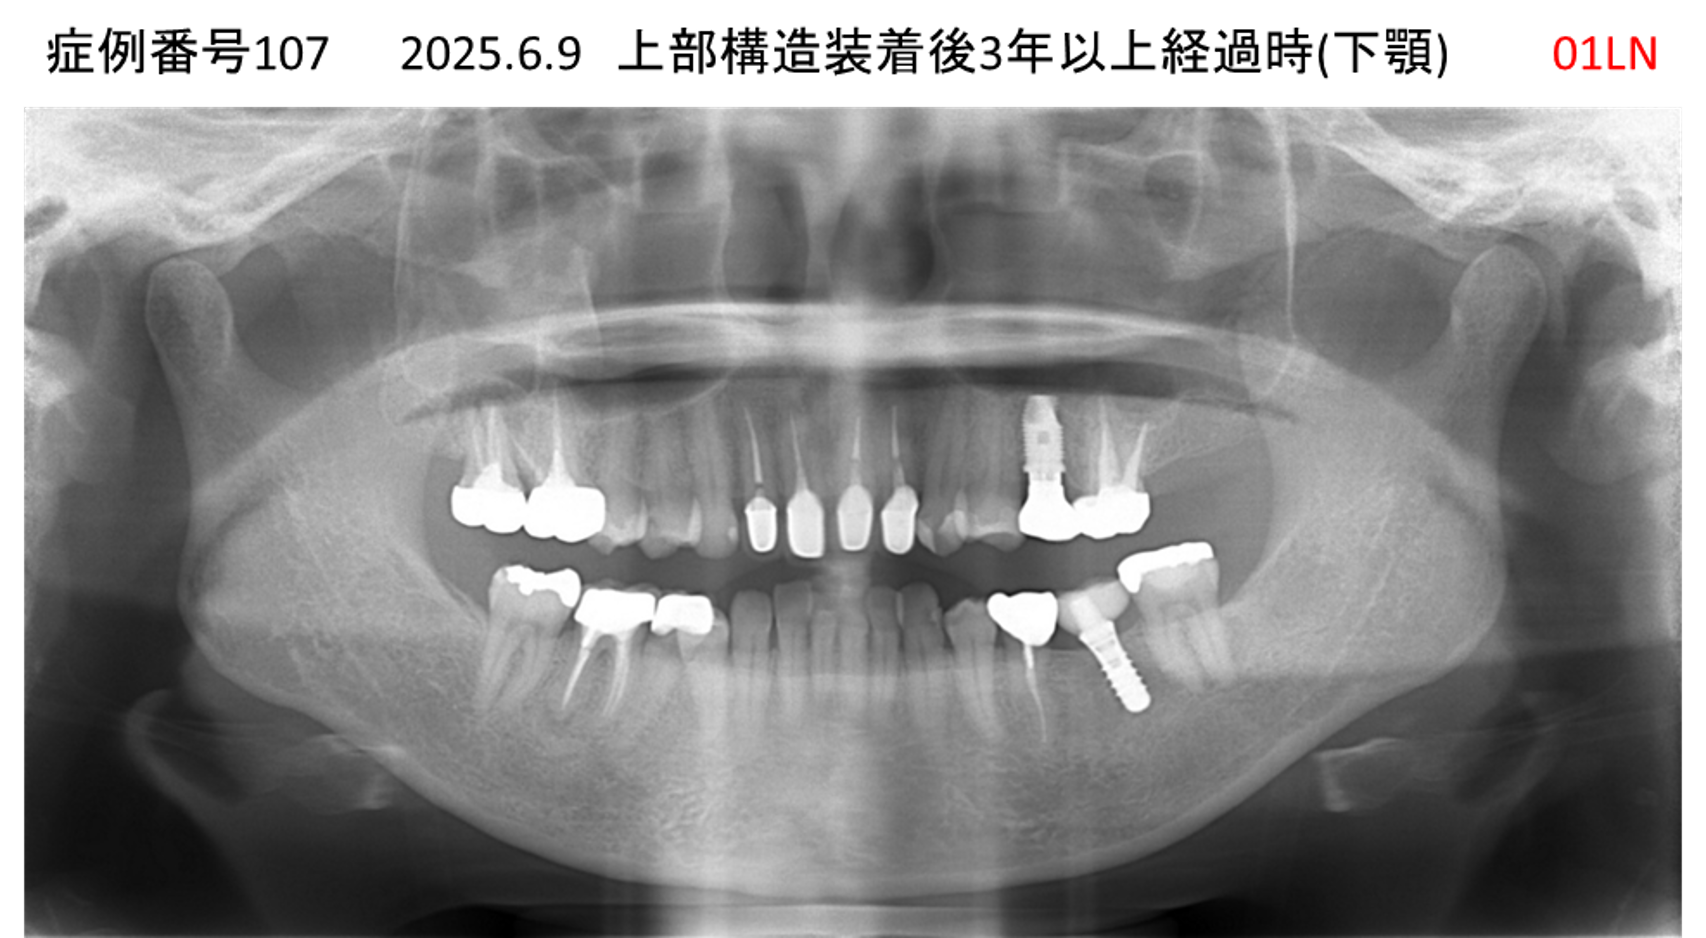

全く噛めない患者様のインプラント症例

| 治療名称 |

インプラントAGC |

| 治療費用 |

860万円+税 |

| 治療期間 |

12か月 |

| 患者さんの症状(主訴) |

全く噛めない、ごはんが後もに食べられるようになりたい、人前で口元を隠したくない |

| 治療内容 |

サイナスリフト、GBR、インプラント、AGC |

| 治療結果 |

しっかり噛めて踏ん張ることができる。食べ物をを選ばなくて済む、何でも食べられる、体重が増えた。見栄えがきれいすぎて自分じゃないみたい |

| 治療の注意点(リスク/副作用) |

インプラントが壊れたら再治療が必要 |